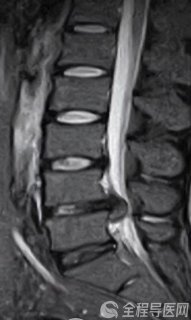

8月上旬的一天,急诊送来了一名胸痛、大汗、心律失常的七旬老人。徐州矿务集团总医院心内科主任祁春梅接诊后为老人做了检查,心电图结果表明,老人有3支右侧心脏血管病变,左心室前降支与回旋支闭塞。判断老人是心急性心梗,情况十分危急。祁主任立刻与家属沟通,建议立即为老人采取手术开通血管。随后经过严密的准备,老人被送入导管室做造影明确病变部位。而造影后的结果却令在场医生震惊,因为老人的左主干在这段时间内竟然发生了病变,全部堵塞!手术台上,老人已经明显感觉更加难受,整个人烦躁、胸闷、十分痛苦。

祁主任立即又与家属进行了二次谈话,阐明了各种利害关系,并说服六神无主的家属立即为老人做左主干开通手术,与生命抢时间。就是在这样的一个突发状况下,祁春梅和她的团队凭借精湛的技术、沉稳的心态、紧密的合作,仅用15分钟就为老人开通了左主干血管,并在接下来陆续开通前降支、回旋支血管,使病人转危为安。